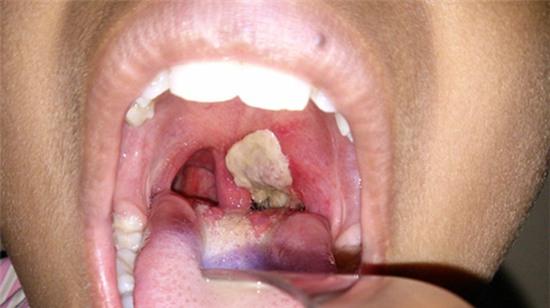

Bạch hầu là một chứng nhiễm trùng nghiêm trọng có ảnh hưởng tới niêm mạc cổ họng và mũi. (Ảnh minh họa: Internet)

Bạch hầu là một chứng nhiễm trùng nghiêm trọng có ảnh hưởng tới niêm mạc cổ họng và mũi. Nếu không được điều trị kịp thời, bệnh bạch hầu có thể gây thiệt hại trầm trọng cho thận, tim và hệ thần kinh. Ít nhất 3% trường hợp trong tổng số bệnh nhân bị bạch hầu sẽ tử vong.

Với bệnh bạch hầu họng thông thường, thời kì nung bệnh thường kéo dài 2-5 ngày mà không có triệu chứng lâm sàng. Khi chuyển sang thời kì khởi phát, các triệu chứng phổ biến thường bao gồm: sốt nhẹ (38-38,5 độ C), sổ mũi 1 hoặc 2 lần, niêm mạc họng đỏ, kém sáng hơn. Xuất hiện những chấm trắng mờ và mỏng, hạch dưới hàm sưng to và đau. Khi chuyển sang thời kỳ toàn phát (2-3 ngày sau), người bệnh cảm thấy khó nuốt, nuốt vướng, đau cổ họng, người mệt mỏi xanh xao, có thể xuất hiện thêm triệu chứng có giả mạc ở mặt sau hoặc 2 bên thành họng, có màu trắng ngà, xám hoặc đen. Giả mạc này thường dai, dính và dễ chảy máu.